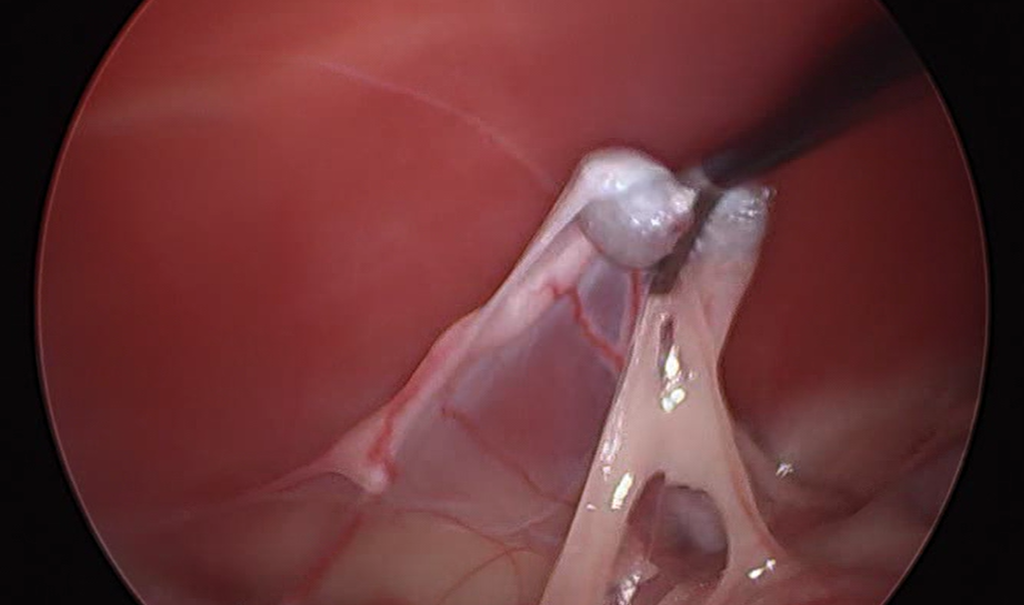

一兩分鐘的翻找後,我們在膀胱的旁邊找到了它,正被小腸和腸系膜覆蓋著,舒服地躺在腹腔深處。

撥開小腸和腸系膜後,就可見到隱睪本人,外觀看起來還算正常,不過我們在術後一定會將這顆睪丸送檢病理中心、確定沒有癌化的可能性。

坐落在腹腔深處的隱睪,術後必須送檢病理切片。

將睪丸提起,以Ligasure燒灼血管叢及精索,接著就可移除它。

Ligasure燒灼的過程要注意不要傷到相鄰的器官。

這顆睪丸外觀看起來很正常,我們就經由trocar的孔洞直接移除它;如果隱睪有癌化的可能(透過術前的超音波、採樣、術中外觀來判斷),那在移除的過程最好要使用取物袋(有點類似捕蟲網),以避免睪丸取出的過程中癌細胞掉落。

找到隱睪後、提起它。